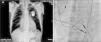

The chest X-ray revealed cardiomegaly and a redundant loop of one of the ventricular leads (Figure 1A). Transthoracic echocardiography showed a moderate circumferential pericardial effusion, severe right atrial dilatation and tricuspid valve (TV) fibrosis with stenosis (functional area 0.6cm2, peak and mean gradient of 16mmHg and 13mmHg, respectively), and mild regurgitation, with no other significant alterations (Figure 2A and B). Transesophageal echocardiography was performed to characterize TV morphology, which revealed marked thickening and reduced mobility of the leaflets and subvalvular apparatus, severely limiting valve opening (mean gradient 12mmHg), and mild regurgitation. Cardiac catheterization showed decreased TV opening, with a mean gradient of 8mmHg and grade II/IV tricuspid regurgitation, with normal pulmonary artery (34mmHg) and right ventricular pressures (Figure 1B). Coronary angiography revealed significant disease of the proximal right coronary artery, but no other significant alterations.